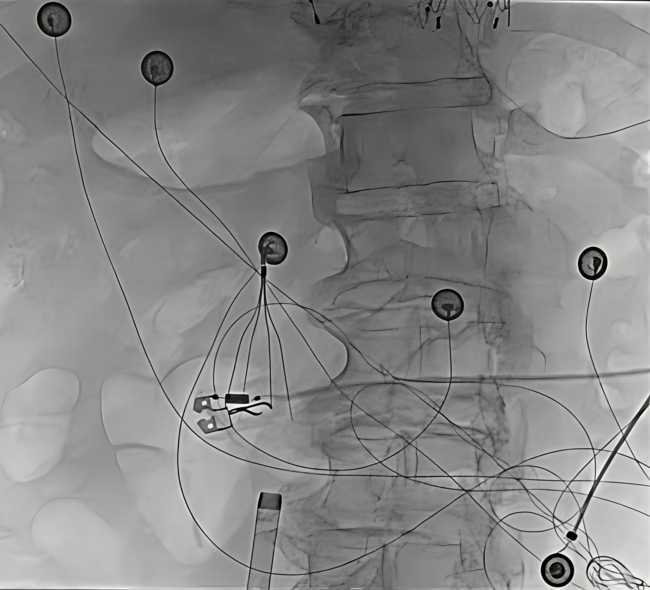

Right Internal Jugular Pulsed Field Ablation for Atrial Fibrillation in a Patient With an Inferior Vena Cava Filter

Video Supplement to "Right Internal Jugular Pulsed Field Ablation for Atrial Fibrillation in a Patient With an Inferior Vena Cava Filter" (Clinical Image).